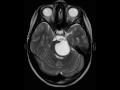

Pilocytic Astrocytoma

8-year-old female with worsening headaches and emesis. There is a predominantly cystic, T1-hypointense, FLAIR mildlyhyperintense, and T2-hyperintense lesion centered within the pons and left brachium pontis. The lesion extends towards the left cerebellopontine angle and prepontine space where there is partial encasement and slight rightward displacement of the basilar artery. On the postcontrast images, there is a minimally enhancing mural nodule along its posteroinferior border. The imaging findings are consistent with a pilocytic astrocytoma. Pilocytic astrocytomas are well-circumscribed, slow-growing lesions, typically demonstrating a cyst with a mural nodule. The cerebellum is the most common site of involvement, followed by the optic nerve and chiasm, and then adjacent to the third ventricle. The differential diagnosis includes medulloblastoma, ependymoma, ganglioglioma and hemangioblastoma.